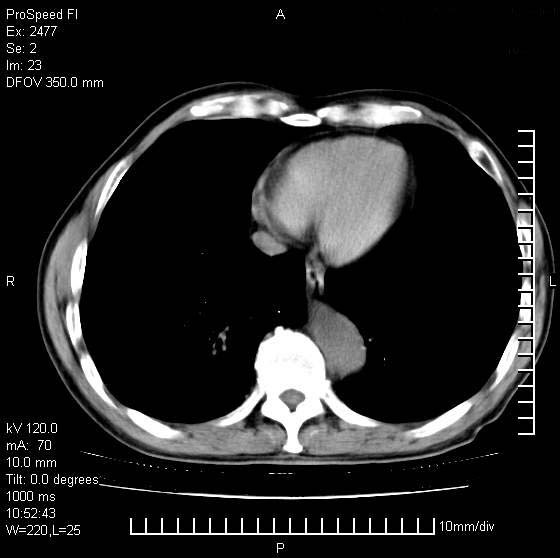

以下是引用天南地北在2007-10-9 14:29:00的发言:[br]1:右上肺结核[br]2:右肺下叶肿块:不支持肺癌,首先考虑炎性病变-肺脓疡可能性大[br]理由:1:临床病史支持,肺脓肿症状不明显应该是不规则服药造成。[br] 2:肿块边缘模糊,周围可见炎性渗出,长毛刺,内见支气管征,不过有点不规则。[br] 我感觉下肺癌这个诊断有点偏左,建议积极抗炎治疗后复查

以下是引用卜一在2007-10-9 15:55:00的发言:[br][br] [br] 1:右上肺结核[br]2:右肺下叶肿块:不支持肺癌,首先考虑炎性病变-肺脓疡可能性大[br]理由:1:临床病史支持,肺脓肿症状不明显应该是不规则服药造成。[br] 2:肿块边缘模糊,周围可见炎性渗出,长毛刺,内见空气支气管征,不过有点不规则。[br] 我感觉下肺癌这个诊断有点偏左,建议积极抗炎治疗后复查![br]支持! [br] [br] [br]

以下是引用wxy7406在2007-10-9 21:02:00的发言:[br]结合临床病史首先考虑感染性病变,但周围型肺癌不能除外,1.患者年龄偏大2.临床有咯血3.(也觉得是最重要的一点)病灶内有偏心性空洞。

以下是引用王仕学在2007-10-9 13:48:00的发言:[br]右下肺周围性肺癌可能性大,最好活检吧

以下是引用hhcckk在2007-10-9 15:18:00的发言:[br]右上肺病灶考虑结核,病灶多种形态并存(纤维化、增殖性病灶并存)[br]右下肺病灶比较难说,个人意见更趋向于“天南地北”的诊断----肺脓肿[br]1、病人有明显的寒战,高热,肿瘤病人很少出现[br]2、病灶周围的肺纹理走向柔和,没有肿瘤病灶常见的集束征[br]3、病灶边缘的毛刺较长,恶性肿瘤多为短毛刺[br]痰中血丝和病人的年龄是两个不利于良性肿块的因素,建议早点活检

以下是引用ydx_74在2007-10-9 15:53:00的发言:[br]右上肺结核,右下中心性肺癌可能大,肺门淋巴结肿大。